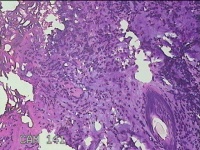

肛周脓壁组织

性别

男

年龄

46岁

临床诊断

1.肛周脓肿 2.混合痔 3.肛裂

一般病史

肛周疼痛2天。

标本名称

大体所见

灰白暗红色不规则碎组织2.2x0.3x0.2cm一块,表面糜烂,位面灰白暗红色,质软。

像良性病变,所提供图片不具有诊断价值。